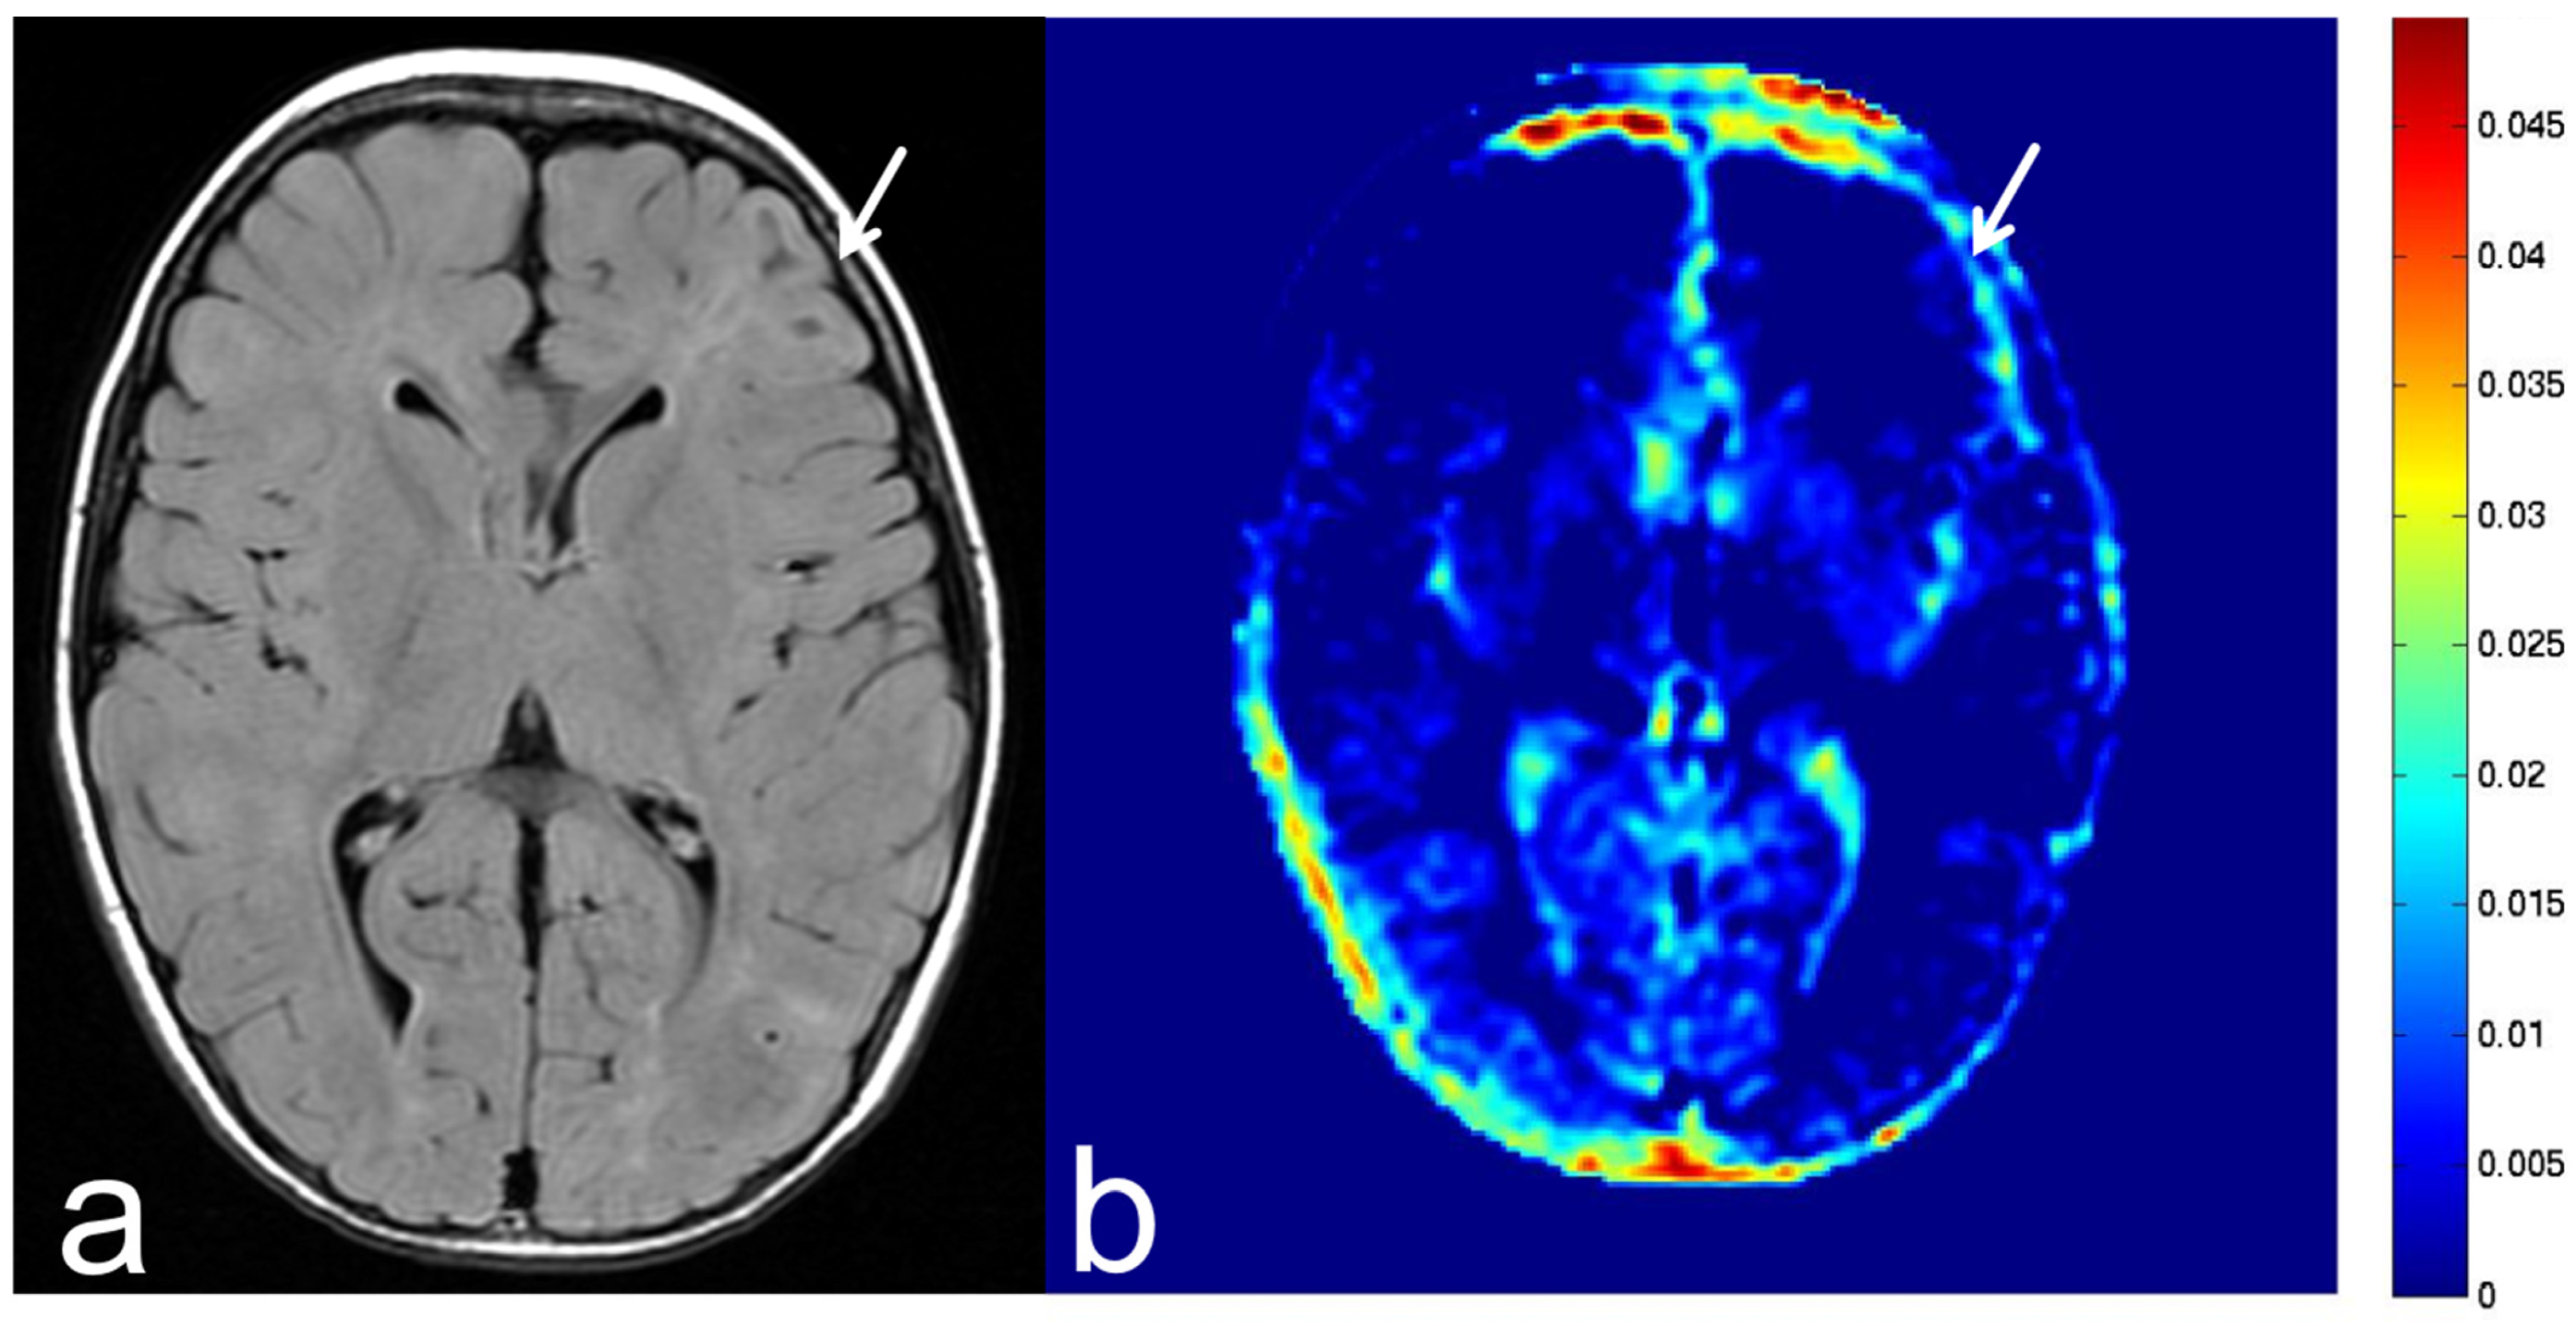

8.5. Hippocampal Sclerosis

9. Discussion

10. Conclusions